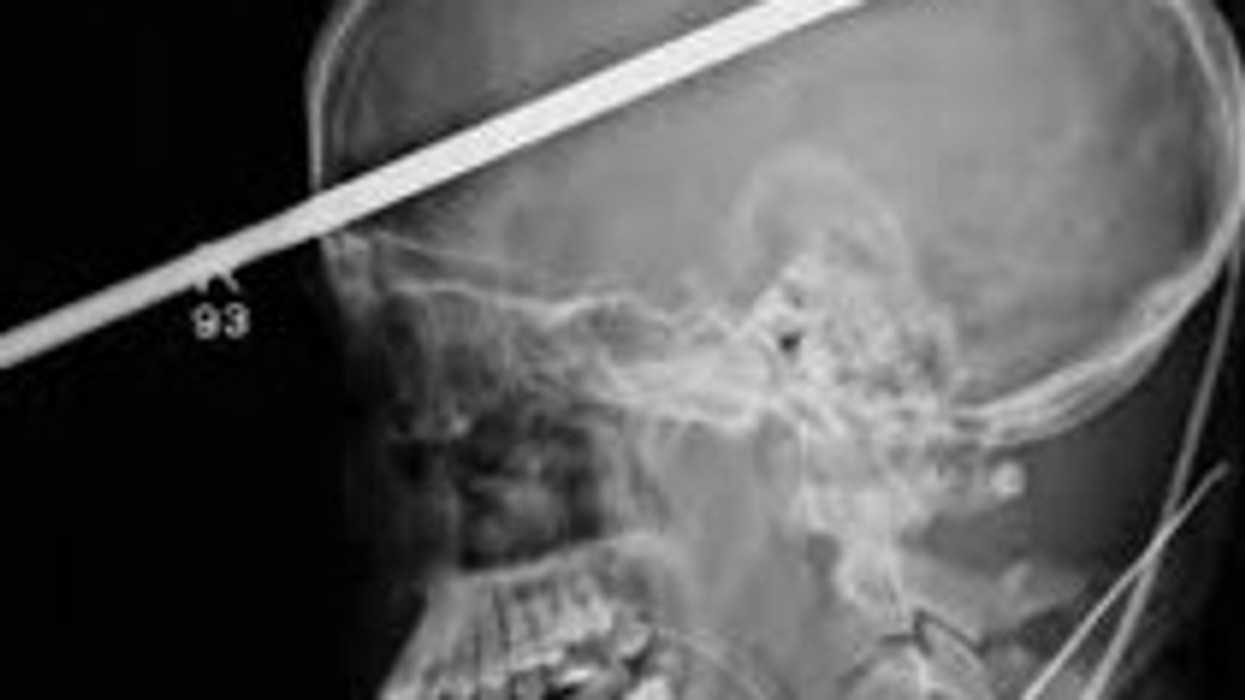

Mjekët e Spitalit "Jackson Memorial" në Miami kanë konstatuar se një shtizë e gjatë 90 centimetra ka depërtuar nëpër trurin e djaloshit Lopez, mbi syrin e tij të djathtë, duke ia shpuar tërësisht kokën.

Pasi i kanë dhënë barëra për qetësim, një pjesë e shtizës prej çeliku duhej të thyhej me një prerës mekanik, që të mund të skanonin kokën e tij.

Shtiza ka shpuar anën e djathtë të trurit, por pa prekur pjesët që kryejnë funksionin e të folurit dhe funksione të tjera të rëndësishme.